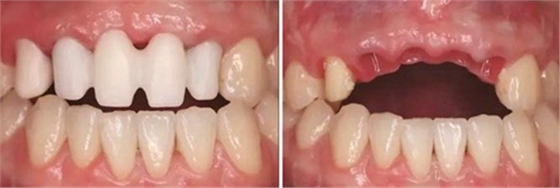

圖29 根管治療后的13行纖維樁修復(fù) 圖30 個(gè)性化轉(zhuǎn)移桿開窗取模

圖31 Index引導(dǎo)下試戴個(gè)性化氧化鋯基臺(tái) 圖32 個(gè)性化氧化鋯基臺(tái)于口內(nèi)就位

圖33 氧化鋯基底于口內(nèi)就位咬合正面觀 圖34 袖口正面觀

(5)2016年1月:軟組織塑形10個(gè)月后,牙齦形態(tài)穩(wěn)定,制取終印模行個(gè)性化全瓷修復(fù)。

①制取個(gè)性化印模帽:首先將臨時(shí)修復(fù)橋體取下后,酒精棉球擦拭干凈,連接相應(yīng)替代體,將該裝置整體插入流動(dòng)性較好的硅橡膠中,待其完全固化后,將臨時(shí)修復(fù)橋體擰松并取下,將硅橡膠內(nèi)的替代體連接開窗轉(zhuǎn)移桿,在硅橡膠制取的穿齦輪廓與轉(zhuǎn)移桿之間用Pattern Resin成型樹脂(GC公司,日本)充填,待成型樹脂凝固后取下進(jìn)行修整拋光,用于最終連于口內(nèi)后制取印模。

②制取開窗印模:13行纖維樁修復(fù)后牙體預(yù)備,排齦后采用DMG Light+Heavy加聚型硅橡膠(DMG,德國(guó))制取開窗式印模,比色,檢查印模制取情況,確認(rèn)準(zhǔn)確無(wú)誤后,連接替代體,涂布分離劑,注入人工牙齦材料,灌注超硬石膏。修復(fù)工藝中心運(yùn)用CAD/CAM計(jì)算機(jī)輔助技術(shù)進(jìn)行設(shè)計(jì),制作個(gè)性化的氧化鋯基臺(tái)以及氧化鋯全瓷修復(fù)體(Wieland威蘭德公司,德國(guó))。